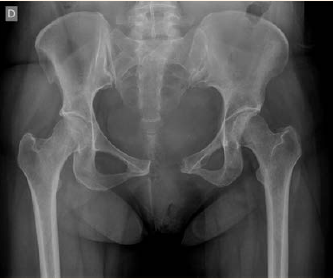

Con el antecedente del dolor ciático y las características del dolor se administró un antiinflamatorio intramuscular (betametasona 12 mg), sin disminución del dolor ni de la incapacidad funcional. La radiografía de pelvis antero-posterior a las 24 horas posparto confirmó una diástasis de sínfisis del pubis severa: distancia entre ambas ramas de 44 mm, sin imágenes sugerentes de fractura y aumento del espacio articular sacroiliaco derecho. Figura 1

Figura 1 Radiografía antero-posterior de pelvis que muestra una distancia entre ambas ramas de 44 mm, sin imágenes sugerentes de fractura y aumento del espacio articular sacroiliaco derecho.